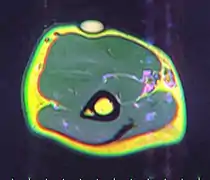

A physical exam is typically the easiest way to diagnose it. Rarely, a tissue biopsy or imaging may be required. The imaging modality of choice is magnetic resonance imaging (MRI) because it has superior sensitivity of distinguishing it from liposarcoma as well as mapping the surrounding anatomy.[22]